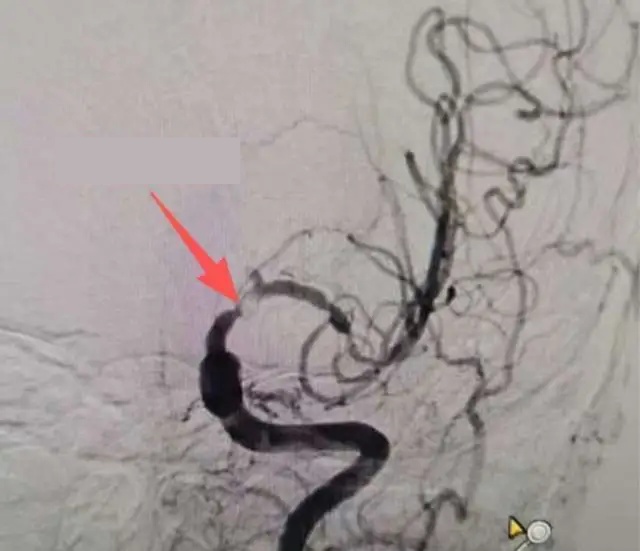

แพทย์เฉินอี้ จากแผนกประสาทวิทยา เปิดเผยว่า ผล MRI พบ มีรอยอุดตันของสมองใหม่ ทำให้เกิดโรคหลอดเลือดสมองแบบ Ischemic คือ โรคหลอดเลือดสมองที่เกิดจากการขาดเลือดไปเลี้ยงสมอง และจากการตรวจหลอดเลือดสมองพบว่า หลอดเลือดสมองซีกซ้ายตีบอย่างรุนแรง หากไม่ได้รับการรักษา อาจทำให้เป็นอัมพาตครึ่งซีกหรือเสียชีวิต

ผลการรักษาแสดงว่า การอักเสบและการตีบของหลอดเลือดสมองดีขึ้นอย่างชัดเจน และไม่จำเป็นต้องผ่าตัดใส่ stent ในหลอดเลือดสมอง นายเหวินยังคงได้รับการติดตามและรักษาต่อที่โรงพยาบาล